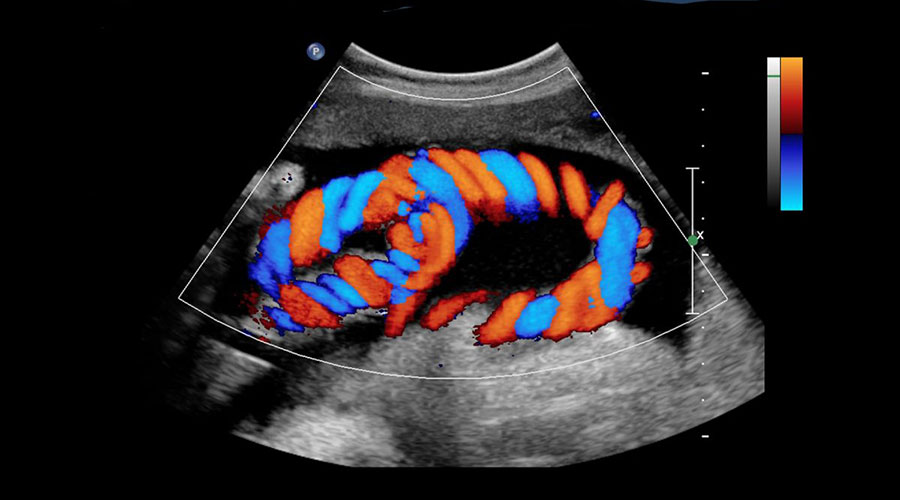

تستخدم تقنية الدوبلر الملون ، وهي إحدى تقنيات التصوير بالموجات فوق الصوتية ، للكشف عن تدفق الدم في الأوعية وصورة الأعضاء داخل الجسم باستخدام موجات صوتية عالية التردد. أولاً ، يتم إرسال الموجات الصوتية عبر المسبار. وبالمثل ، يتم جمع الموجات الصوتية العائدة بواسطة المسبار وتحويلها إلى طاقة كهربائية. يتم تحويلها أيضًا إلى صورة بواسطة الكمبيوتر. يتم استخدامه في فحص أجزاء كثيرة من الجسم. مجالات الاستخدام الرئيسية هي ؛ ويمكن تلخيصها على أنها أعضاء داخل البطن ، وأعضاء سطحية مثل الغدة الدرقية ، والثدي ، ومتابعة الحمل ، والقلب ، والشرايين ، والأوردة.

في مركزنا ، يتم استخدام أجهزة الموجات فوق الصوتية مع التكنولوجيا التي طورتها GE (Logic 9) وشركات Siemens (Antares ، Sequia) بين عامي 2003 و 2005 ويتم تنفيذ درجاتها الأعلى بشكل مستمر. يمكن تشخيص وعلاج العديد من أمراض المراحل المبكرة التي لم تتم رؤيتها من قبل. بفضل الدقة العالية ، يسهل إجراء الخزعة الموجهة من الولايات المتحدة ويوجه العلاج.